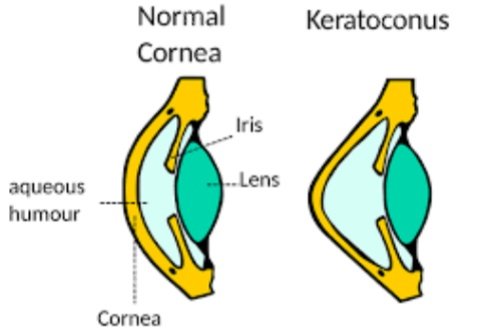

圆锥角膜交联手术哪家强?爱尔眼科、普瑞眼科、华厦眼科、朝聚眼科、新视界眼科都是做圆锥角膜交联手术口碑好的正规眼科医院!

早期圆锥角膜:单用交联术稳定角膜形态

中期病例:交联术联合板层移植,术后视力提升明显

晚期患者:穿透性移植联合生物工程角膜,降低排斥风险